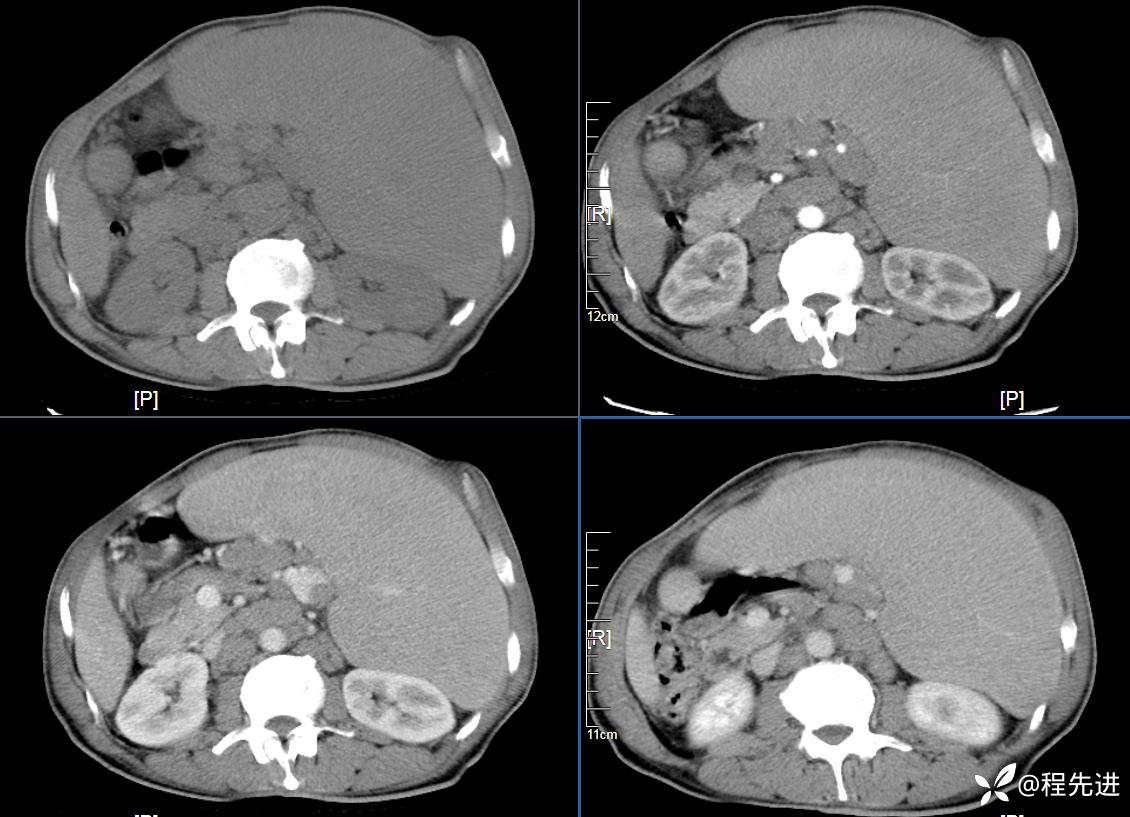

CT平扫及增强3期: